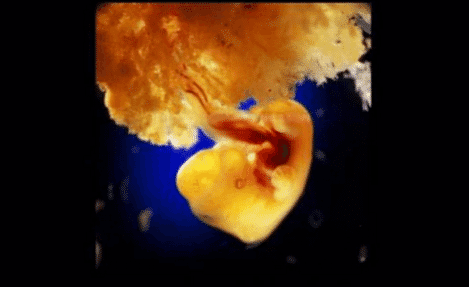

C’est en collaboration avec des médecins que le photographe Lennart Nilsson a passé 12 ans à suivre le développement de fœtus depuis leurs conceptions jusqu’à leurs naissances ! Son projet est incroyablement documenté et très parlant ! Il nous offre ici une vision du miracle de la vie totalement inédite ! Ces photos ont été prises avec un endoscope et un microscope à balayage électronique . Nilsson est un pionnier de la photographie médicale ! Il a pris le premier cliché de ce type en 1965.

Les photos ci-dessous sont d’une précision incroyable. On part vraiment du tout tout début comme dans les livres pour enfants sur la reproduction : quand le spermatozoïde rencontre l’ovule. On a beau trouver ça enfantin, c’est bien comme ça que ça commence. Et cette étape est le début d’une multitude de petites étapes qui vont permettre au foetus de se développer. Au début évidemment, le foetus ne ressemble en rien à un bébé comme on les connait. Mais on peut voir qu’à partir de 10 semaines environ, tout s’accélère. Le foetus a de plus en plus une apparence de bébé et pendant les mois qui suivent, les organes vont se développer.

11. 40 jours de développement